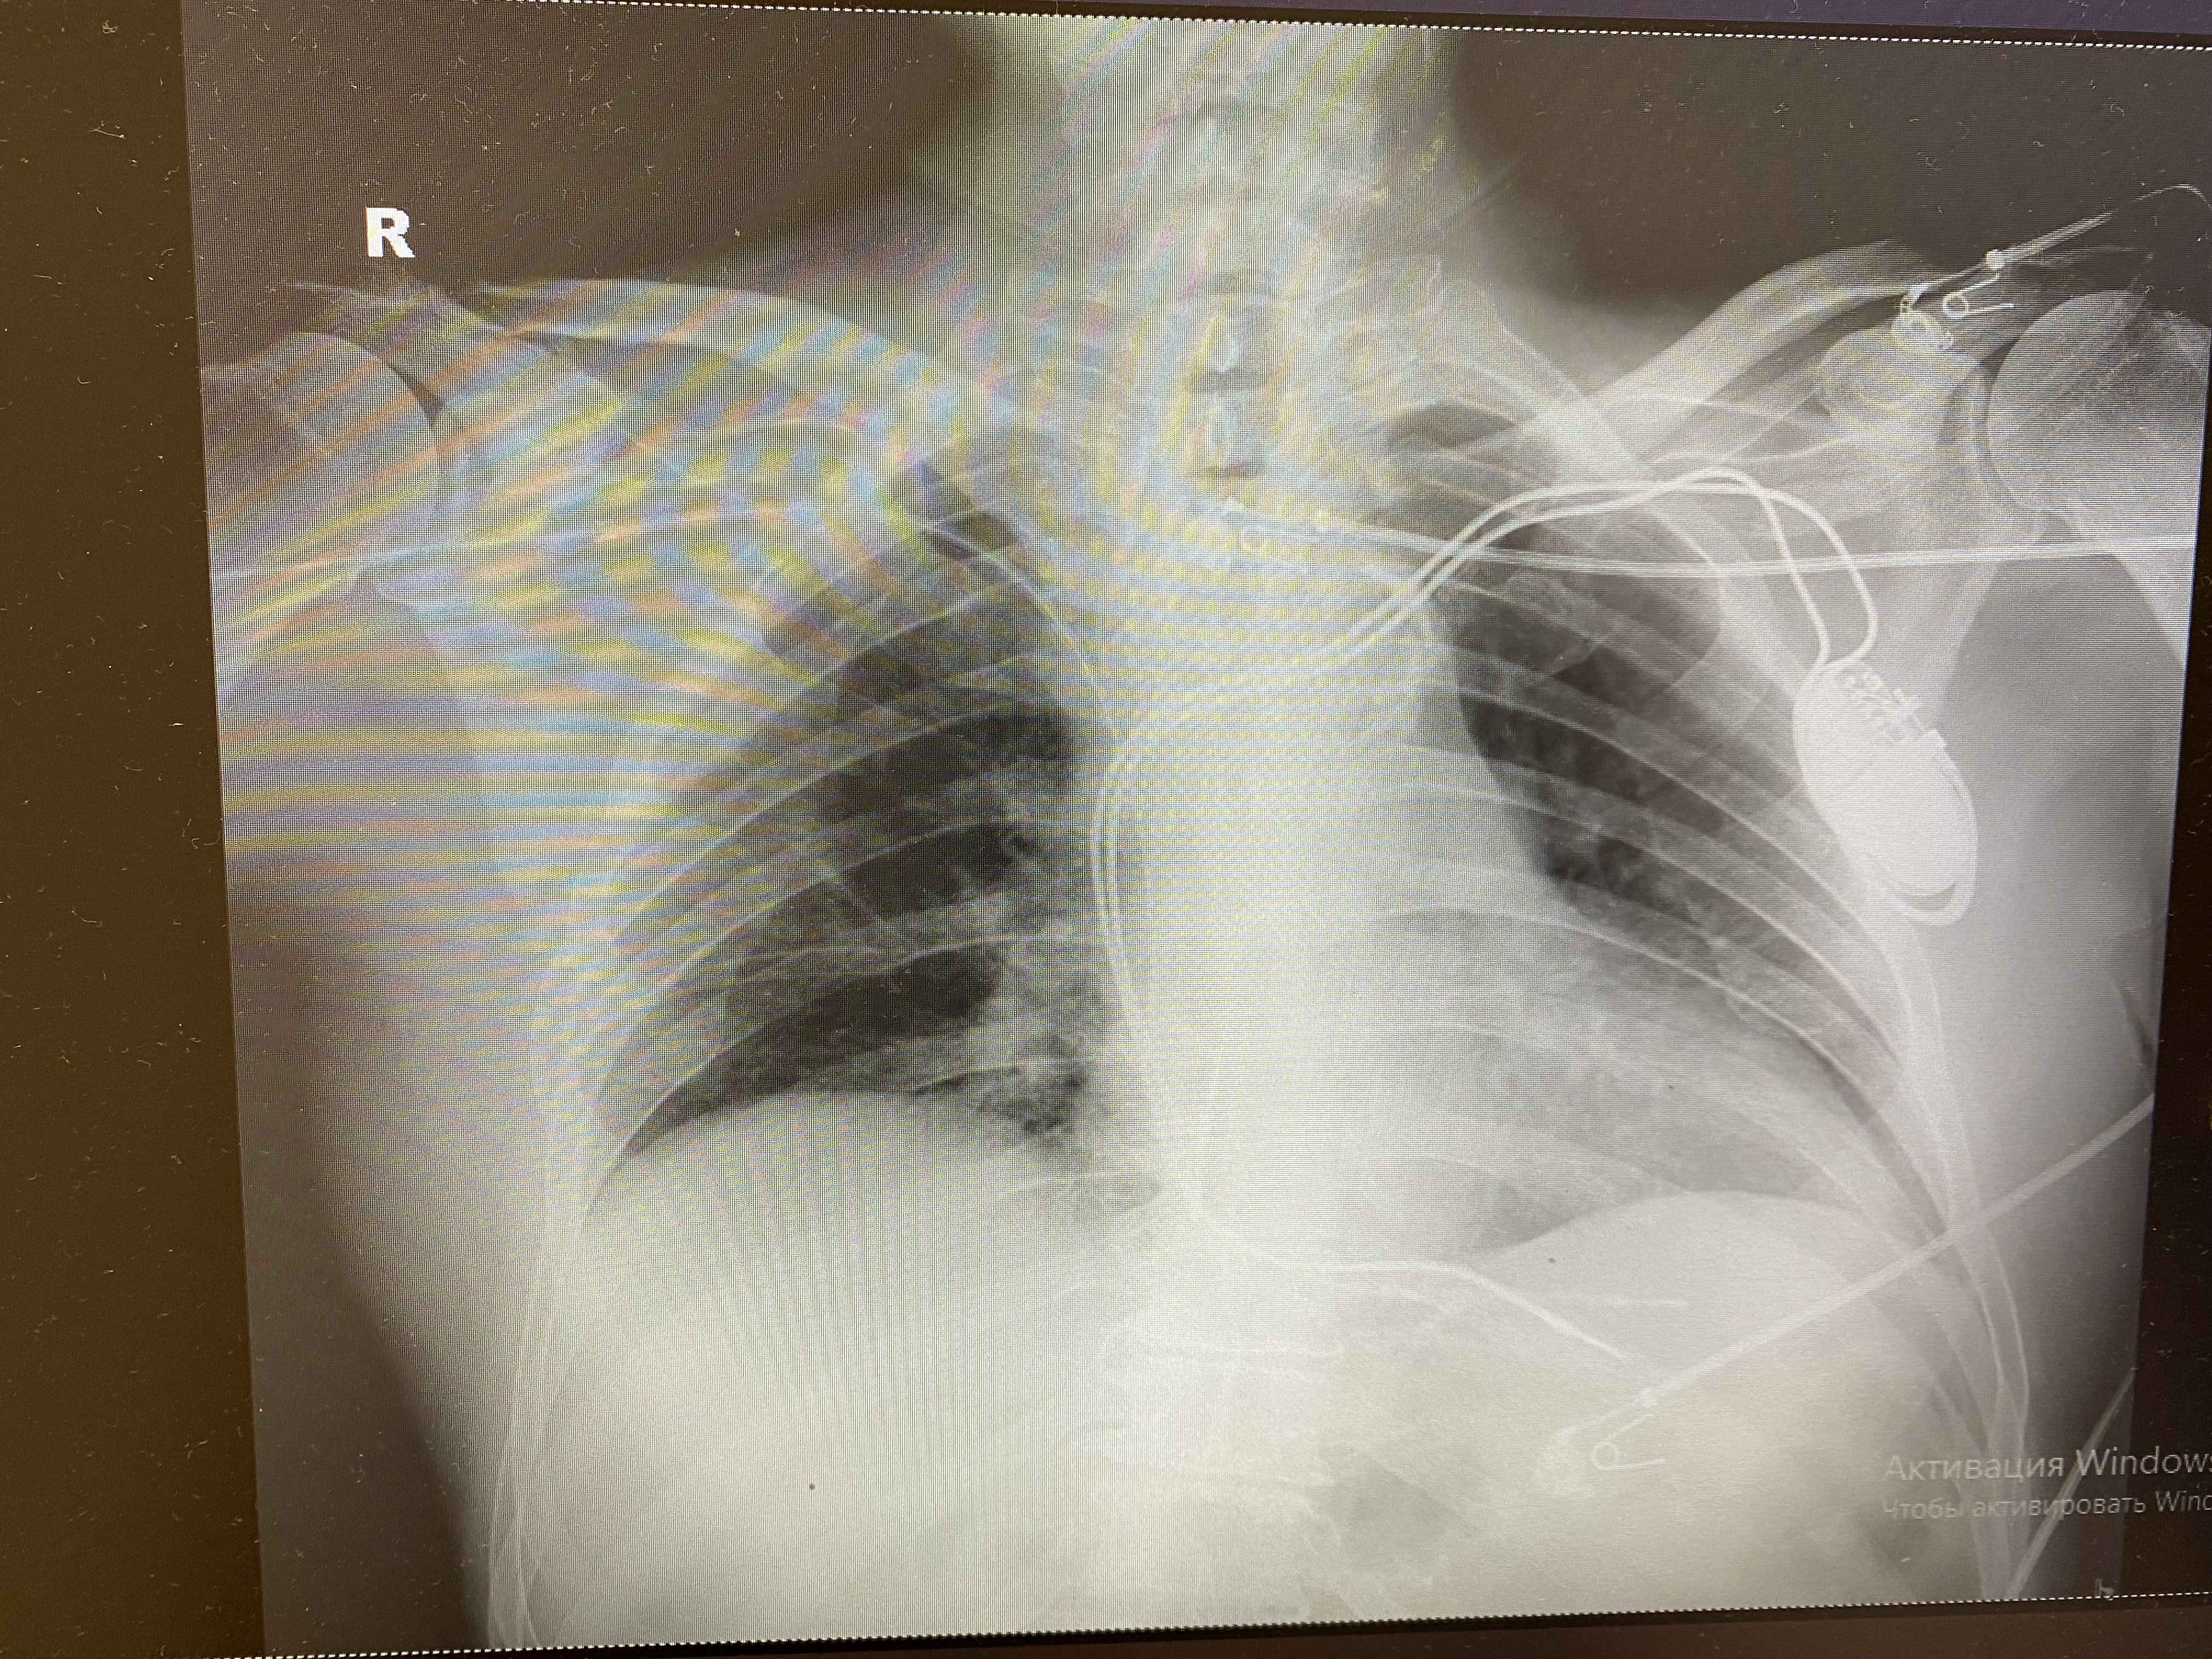

Работа времянки и постоянный вдруг ожил

IMG_0840.jpg

IMG_0840.jpg [ 1.73 MiB | Просмотров: 8174 ]

IMG_0846.jpg

IMG_0846.jpg [ 5.55 MiB | Просмотров: 8174 ]